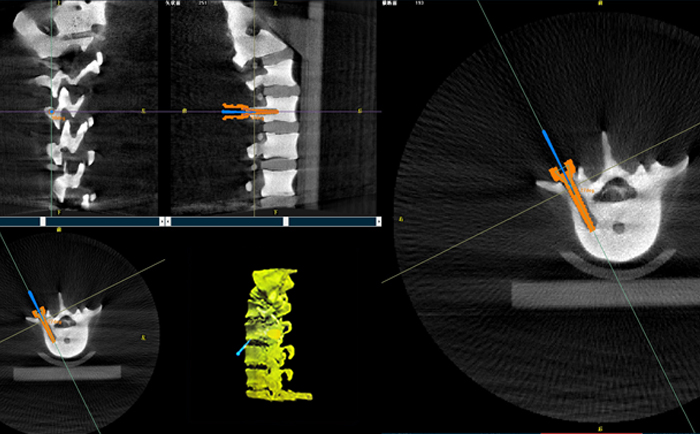

在一臺機器人輔助下的脊柱手術(shù)中,使用三維C形臂與機器人匹配,僅15秒左右就能獲得患者病變脊柱部位的高清3D圖像,機器人輔助手術(shù)可準(zhǔn)確定位病變部位、置入椎弓根螺釘位置等。

目前脊柱外科應(yīng)用最廣泛的還是機器人輔助置入椎弓根螺釘。主刀大夫可以通過該3D圖像確定手術(shù)中椎弓根螺釘?shù)倪M釘點、置釘方向以及置釘深度。緊接著,在機器人手術(shù)系統(tǒng)的導(dǎo)航下,該機械手臂能夠準(zhǔn)確移動到定位椎弓根螺釘?shù)戎冕斘恢茫t(yī)生只需要在置釘部位切開一個1cm切口,沿著機械臂所指方向鉆入導(dǎo)針,并沿導(dǎo)針按置入椎弓根即可,從而使椎弓根螺釘能夠以最理想化的方式打入,保證患者的安全和手術(shù)有效性。